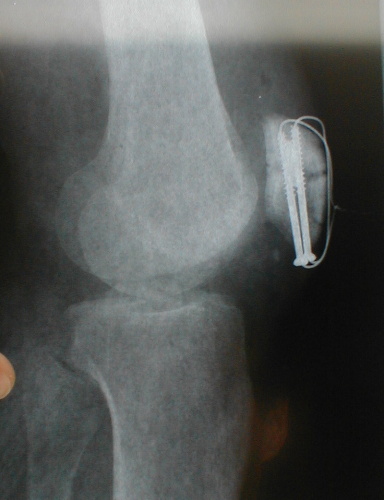

This hurt.